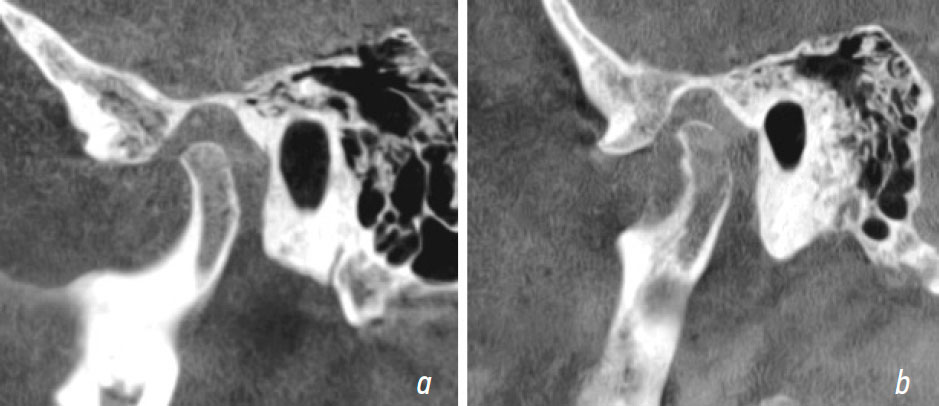

После 6 мес. лечения пациенту провели оценку положения головок нижней челюсти с каппой по данным КТ (рис. 6, 7).

Рис. 6. Правый височно-нижнечелюстной сустав после лечения с каппой

Fig. 6. Right temporomandibular joint after using the splint

Рис. 7. Левый височно-нижнечелюстной сустав после лечения с каппой

Fig. 7. Left temporomandibular joint after using the splint